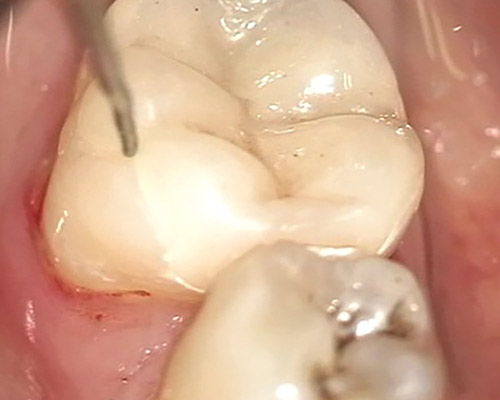

As part of endodontic therapy, we treat root canals using a combination of manual and machine techniques according to the latest research, while the quality of our work is incomparably enhanced by the use of a microscope. By investing in high-quality devices and instruments, we guarantee high success rates of endodontic treatment.

We perform post-endodontic therapy according to indication by reinforcing the endodontically treated tooth with a glass fiber post (fiber post) or a laboratory-made metal post.

Root canal treatment (also called endodontics) is necessary when the blood and nerve supply of the tooth (known as the pulp) is infected by decay or injury. You may not feel pain in the early stages of infection.

In some cases where the tooth darkens, we can conclude that the tooth nerve has died (or is dying). In this situation, root canal treatment is necessary. If the dental pulp becomes infected, the infection can spread through the root canal system of the tooth to the surrounding bone and eventually lead to an abscess.

An abscess is an inflamed area where pus collects, causing later swelling of the tissues around the tooth. Abscess symptoms can range from a dull ache to severe pain, and the tooth may be sensitive when biting.

If root canal treatment is not performed, the infection will spread and extraction will be required. Root canal treatment, or endodontics, cleans the infected pulp chamber and treats the damage. In this way, it is possible to save the tooth.